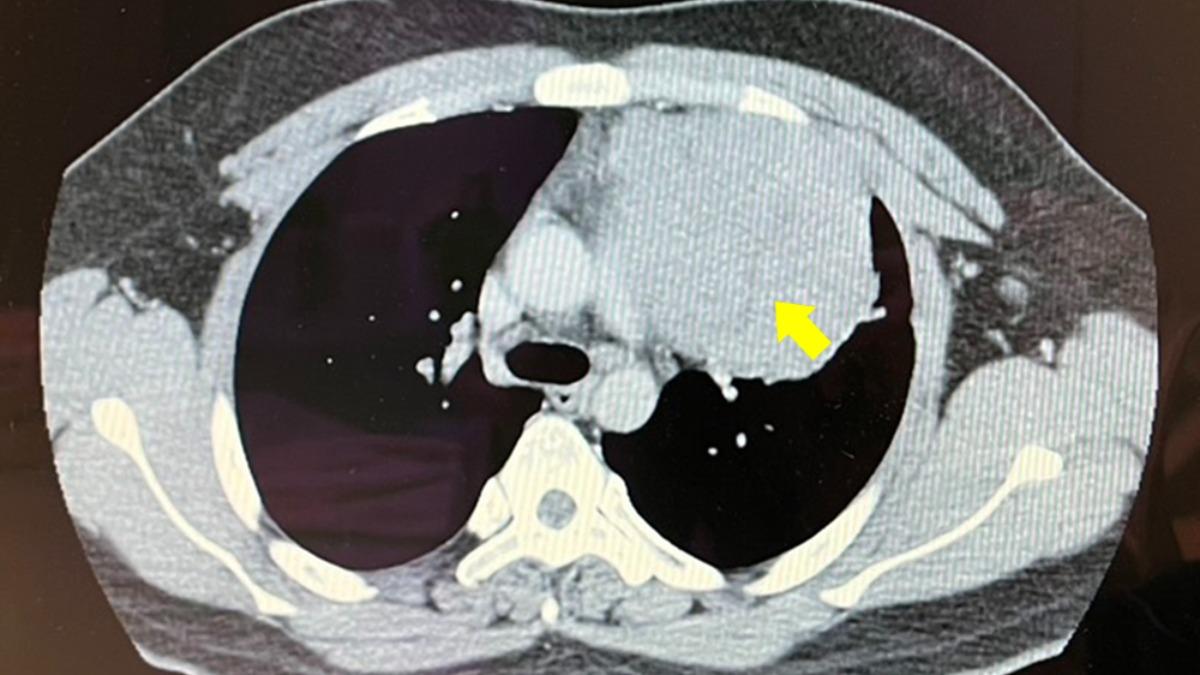

而接著少年緊急住院接受更精密檢查,包括做切片先確認腫瘤性質,接著進行胸部核磁共振造影以確定沒有侵犯心包膜,及腫瘤與心臟、肺臟的黏著程度,另外考量腫瘤疑似生殖細胞瘤,也做了腹部斷層掃描,耗費一番工夫確診為罕見的「縱膈腔精細胞瘤」。

主治醫師賴重佑解釋,「縱膈腔精細胞瘤」常是不明原因在性腺外的器官產生癌變,回顧國內文獻,有些醫學中心都有零星個案報告,確實屬於罕見疾病。

起初醫療團隊認為,少年腫瘤無轉移與血管侵犯情形,計劃是使用達文西機械手臂經劍突下協助執行此困難且複雜的手術,但因少年器官沾黏相當嚴重,決定改以傳統正中胸骨切開賴重佑進行腫瘤的切除,將12公分腫瘤連帶部分左肺做移除,最後腫瘤重達550公克。